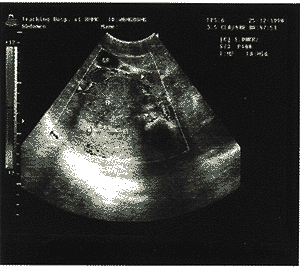

图1 巨大肿块,包膜完整有声晕包绕,内部

呈分叶状,互相融合光团回声

中国超声医学杂志990731 患者女性,11岁,右上腹部持续性隐痛,呈阵发性加重3天入院。查体:腹部平坦,右 上腹部轻压痛,无反跳痛,肝区稍膨隆,肝浊音,上界第4肋间,下界位于右肋缘下8cm,质 中等,边缘不规则,有轻叩击痛,无移动性浊音,脾、双肾无异常。X线提示:右膈面升高 ,疑膈下病变。CT扫描诊断:肝右叶巨大出血性囊实性肿瘤:囊腺癌或囊腺瘤可能性大,寄 生虫病待排除。彩色B超显示为:肝上界第4肋间,下界位右肋缘下8.2cm,肝体积增大,肝 右后叶可见1个形态类似圆形的巨大团块回声,约16cm×12cm×10cm,肿块周边清晰,有声 晕包绕,包膜完整,内部回声高低不均匀,呈分叶状、互相融合性光团回声(图1)。胆囊和 门脉右支受压前移,彩色多普勒显示肿块周边可见绕形血流,肿块内见稀少星点状血流信号 (图2)。脾形态正常,厚3.4cm,实质回声均匀。超声诊断为:肝右后叶巨大实质性占位性 病变:考虑为右后叶肝内巨块型恶性肿瘤。手术所见:肝右后叶及部分前叶,约20cm×16cm ×12cm巨大实质性病变,肿物包膜完整,内部如烂鱼肉样,含少量液体,部分为陈旧性血性 液,部分扩展至左内叶肝后部,左外叶肝代偿性增大,包膜正常,脾、胃、十二指肠及胰腺 、盆腔均未见异常,周围淋巴结未见肿大,无腹水。手术切除肿块重1500克左右,加肝右叶 半部共重量2000克。送病理检查。病理报告:肝脏恶性肿瘤:考虑①肝恶性纤维组织细胞瘤 ;②肝未分化肉瘤。